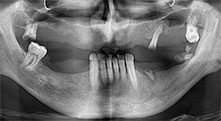

Für welche Indikationen verwenden Sie die Sägen?

Bratu: Wir nutzen die Instrumente routinemäßig für die Entnahme von Knochenblöcken und das Spalten von Kieferkämmen. Weiterhin osteotomieren wir mit den Piezomed B6/B7 retinierte Zähne und entfernen nicht erhaltungsfähige Implantate. Alles Indikationen, bei denen es auf tiefe, saubere Schnitte ankommt.